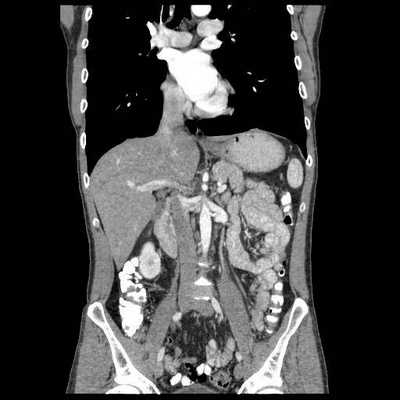

рис. 1-3 По данным МСКТ органов брюшной полости с в/в контрастированием: признаки объёмного образования на уровне мезогастрия (среднего этажа брюшной полости), связанное со стенкой тонкой кишки (дивертикул подвздошной кишки?).

Клинический диагноз:

Основной: Дивертикул подвздошной кишки.

Осложнения: перфорация дивертикула подвздошной кишки. Абсцесс брюшной полости.

Пациентка оперирована в плановом порядке в объеме лапароскопически-ассистированной резекции тонкой кишки. Лапароскопическойхолецистэктомии. Аппендектомии. Энтероэнтеростомии. Дренирования брюшной полости.

При проведении операции у пациентки было выявлено объемное образование, расположенное в мезогастрии с вовлечением стенки тощей кишки на нескольких участках. При вскрытии данного образования было выявлено наличие инородного тела (марлевая салфетка).

Из данного клинического случая можно сделать вывод:

для диагностики инородного тела крайне важным является сбор анамнеза с указанием предшествующей хирургической операции. При подозрении на наличие у пациента инородного тела МСКТ позволяет визуализировать в образовании пузырьки газа диаметром от 1,5 мм, оценить степень изменений в окружающей жировой клетчатке, взаимоотношение инородного тела с прилежащими органами, косвенно оценить наличие кровотока в подозрительном образовании.